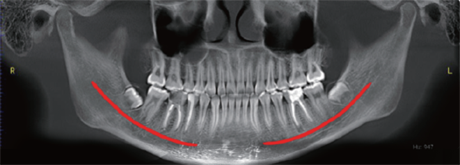

Additionally, the system provides three flexible scan modes to match clinical needs. Multiple focus layers in panoramic imaging fit each patient’s dental arch perfectly.

Multiple focus layers in panoramic imaging, fitting the patient’s dental arch

Multiple focus layers in panoramic imaging, fitting the patient’s dental arch -

Furthermore, AI+PAN Dental CBCT Imaging enhances precision.

- The system rebuilds panoramic views directly from CBCT data using AI.

- Panoramic auto-focus and multi-layer technology select the best curve automatically.

- Therefore, the final image is cleaner and easier to read.